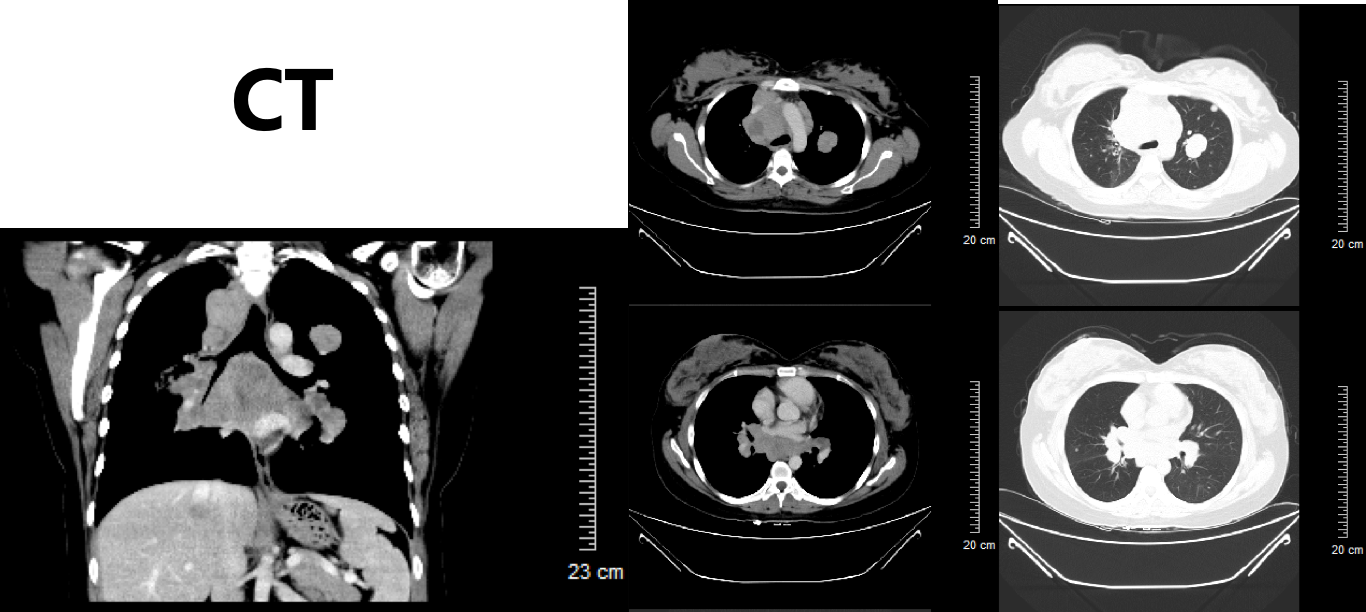

患者初治时行PD-L1(22C3)检测提示PD-L1高表达为95%,故建议患者行三线免疫治疗。由于药物可及性,患者综合考虑后,选择信迪利单抗。患者于2019-04-04、2019-04-26、2019-05-18分别行第1~3周期免疫联合化疗三线方案(信迪利单抗+白蛋白紫杉醇 ,每3周1次)。2019-05-18复查肺部CT如图6所示,2019-05-18复查CT:肺部病灶较前明显缩小,阻塞性肺炎较前好转、肝脏病灶较前明显缩小。T2、T9-L2椎体及L2左侧附件多发骨转移同前。

图6 2019-05-18复查胸腹部CT提示肺部病灶较前明显缩小,阻塞性肺炎较前好转、肝脏病灶较前明显缩小。T2、T9-L2椎体及L2左侧附件多发骨转移基本同前

患者于2019-06-12、07-08继续行第4-5周期三线方案(信迪利单抗+白蛋白紫杉醇 ,每三周一次),2019-07-26复查胸腹部CT提示,肺部病灶较前明显缩小,肝脏病灶较前明显缩小。T2、T9-L2椎体及L2左侧附件多发骨转移同前(图7)。患者肿瘤标志物也基本呈现下降趋势(图8),疗效评价为(PR)。

image027.jpg

image029.jpg

图7 2019-07-26复查胸腹部CT提示,肺部病灶较前明显缩小,肝脏病灶较前明显缩小。T2、T9-L2椎体及L2左侧附件多发骨转移同前